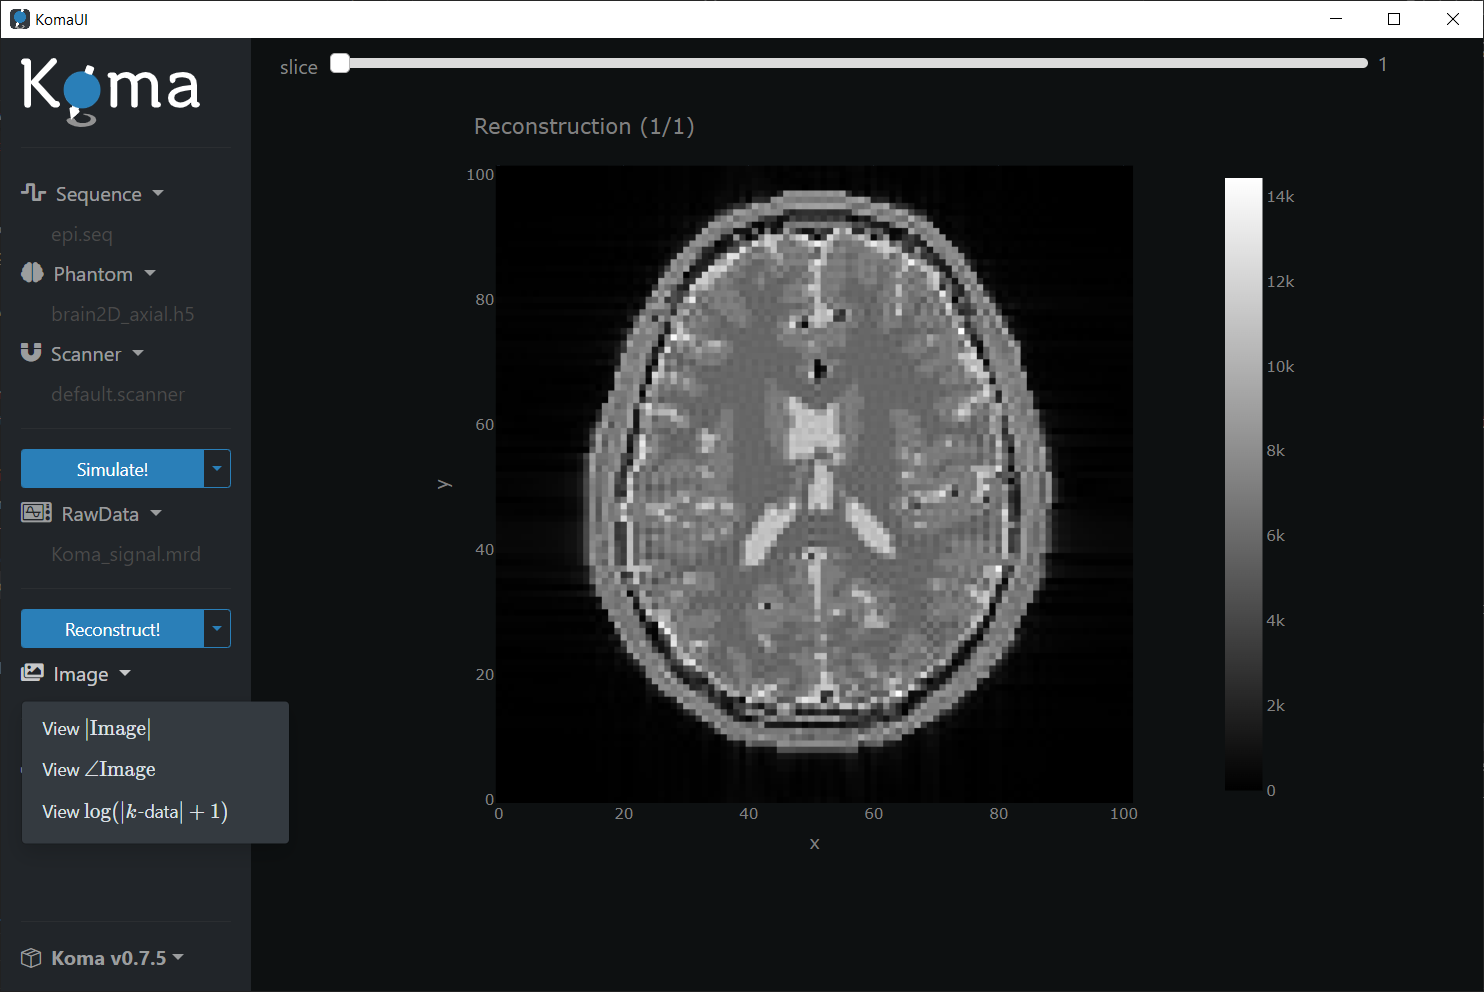

Visualization of the Image

Press the Reconstruct! button to perform the reconstruction (this may take a while). Automatically the generated Image should be displayed or you can click on the he Reconstruct! dropdown and then press the |Image| button: